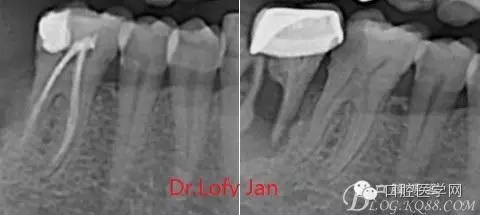

前言:自己做的一些曲面斷層片在未試尖根管治療中的病例整理,發(fā)現(xiàn)問題很多包括自身的,技術(shù)的,還有設(shè)備的問題,予以總結(jié)整理并期待進(jìn)一步提高。

根管治療術(shù)是牙體牙髓疾病治療中最復(fù)雜和最關(guān)鍵的治療項目。根管充填材料抵達(dá)根尖、并能嚴(yán)密堵塞根尖孔,是確保根管治療效果的關(guān)鍵指標(biāo)。為了保證根管充填到位,醫(yī)生需要在術(shù)前照牙片以了解牙根根管的數(shù)量、彎曲程度和長度,在術(shù)中有時需要插針照牙片來精確測量根管長度,術(shù)后必須照牙片以確定是否根管充填到位,如果欠填或超填,就需要重新充填、重新照牙片確認(rèn),直到根管充填到位。所以,在患者接受根管治療時有時會反復(fù)照牙片。

《數(shù)字化根尖片、曲面斷層片、CBCT測量牙齒長度準(zhǔn)確性的比較研究》文中顯示:平行投照數(shù)字化根尖片影像長度和牙齒實際長度之間無顯著性差異(P0.05);數(shù)字化曲面斷層片影像長度和牙齒實際長度之間有顯著性差異(P0.05),平均失真率為17.05%。CBCT冠狀面測量結(jié)果中除上頜前磨牙區(qū)、下頜前磨牙區(qū)與真實長度差異無統(tǒng)計學(xué)意義(P0.05)外,其余6個分區(qū)差異均有統(tǒng)計學(xué)意義(P0.05);矢狀面測量結(jié)果中上頜磨牙區(qū)、下頜磨牙區(qū)、下頜前磨牙區(qū)、下頜尖牙區(qū)、下頜前牙區(qū)與真實長度比較差異均有統(tǒng)計學(xué)意義(P0.05)。結(jié)論平行投照數(shù)字化根尖片較曲面斷層片和CBCT能更加精確地反映牙齒的真實長度。

病例分析:曲面斷層片在x線輔助診斷與檢查中目前大多數(shù)文獻(xiàn)和著作都建議只能作為初診拍片檢查手段,不能作為終末疾病的確診與手術(shù)療效的評價指標(biāo),臨床大部分中小型門診都因為設(shè)備不齊全導(dǎo)致信息偏差很大。